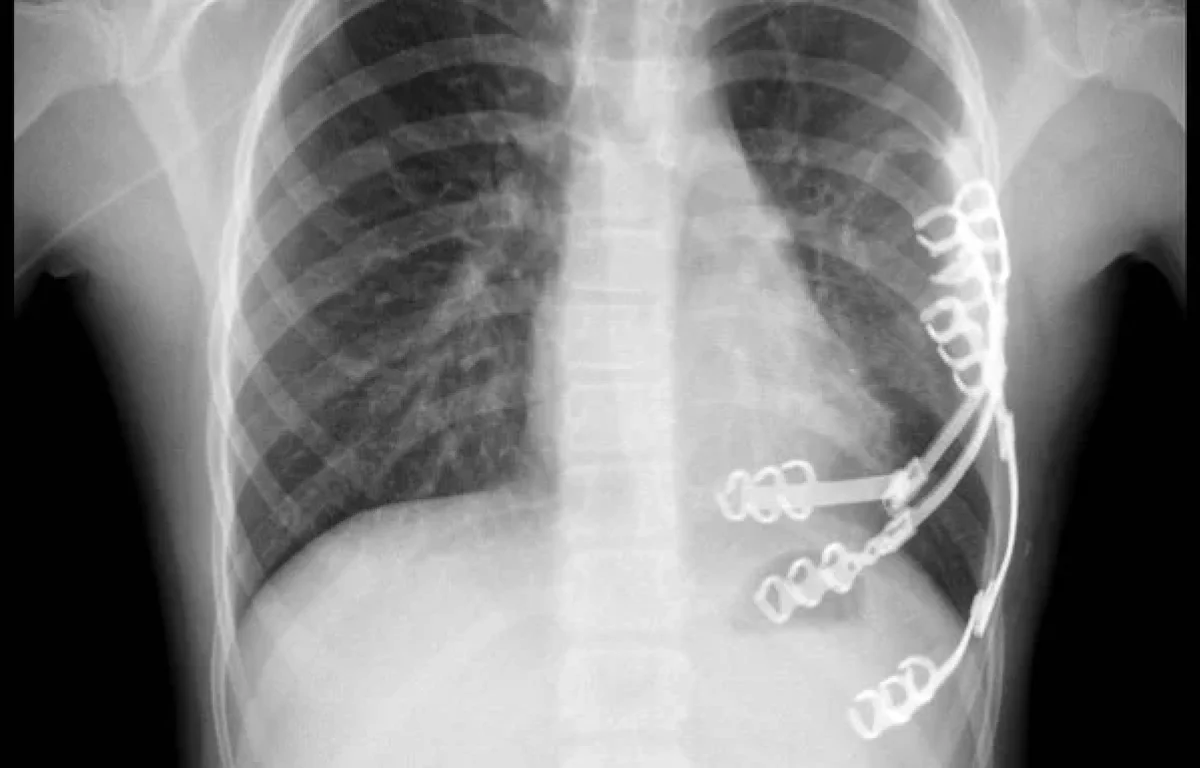

ויולטה הגיעה לישראל במסגרת תיירות מרפא, לאחר שהגידול בגופה הפך בלתי ניתן לשליטה. במשך חודשים עברה תשעה סבבים של כימותרפיה, עד שניתן היה לגשת לניתוח. הסרת הגידול כולו יחד עם חלק מכלוב הצלעות שנפגע, והשתלת שתלים מיוחדים עשויי טיטניום במקומו.

מדובר בניתוח ראשון מסוגו בבית החולים, שנוהל בשיתוף פעולה בין צוותים מבתי החולים שניידר ובילינסון, בהובלת דוקטור יורי פייסחוביץ מבילינסון ודוקטור מיכאל סגל משניידר.